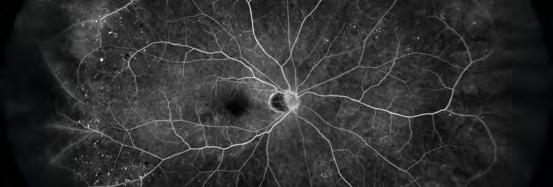

• Captura de detalles nítidos de la estructura vascular desde la fase temprana a la tardía de la angiografía con fluoresceína.

Angiografía con Fluoresceína

Angiografía con fluoresceína de retinopatía diabética proliferativa